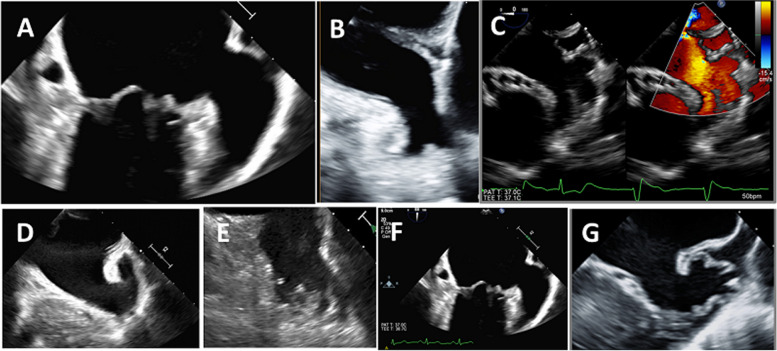

心肌栓塞性中风是心房颤动(房颤)最严重、最危及生命的并发症,12 个月的相关死亡率高达 30%。瓣膜性房颤中约 47% 的血栓和非瓣膜性房颤中 91% 的血栓位于左心房附壁(LAA)。因此,在许多临床情况下,识别或排除 LAA 血栓至关重要。在房颤消融术和 LAA 封堵术等介入手术之前、期间和之后,使用成像模式(尤其是超声心动图)评估 LAA 形态和功能至关重要。这篇综述文章介绍了 LAA 的解剖、生理和病理背景,随后对不同的超声心动图模式进行了评估。其中包括许多实用要点,以提高诊断准确性并尽量减少图像采集和解读过程中的误差。在每个以 LAA 为关键目标的临床场景中,都收集了具体而重要的信息和参数。

Cardioembolic stroke is the most serious and life-threatening complication of atrial fibrillation (AF), with an associated mortality up to 30% at 12 months. Approximately 47% of thrombi in valvular AF and 91% of thrombi in nonvalvular AF are localized in the left atrial appendage (LAA). Therefore, identification or exclusion of LAA thrombi is critical in many clinical situations. It is essential to assess LAA morphology and function using imaging modalities (particularly echocardiography) before, during, and after interventional procedures such as AF ablation and LAA occlusion. This review article describes the anatomical, physiological, and pathological background of the LAA, followed by an assessment of different echocardiographic modalities. Many practical points are included to improve the diagnostic accuracy and to minimize errors during image acquisition and interpretation. In each clinical scenario where LAA is the crucial target, specific and essential information and parameters are collected.